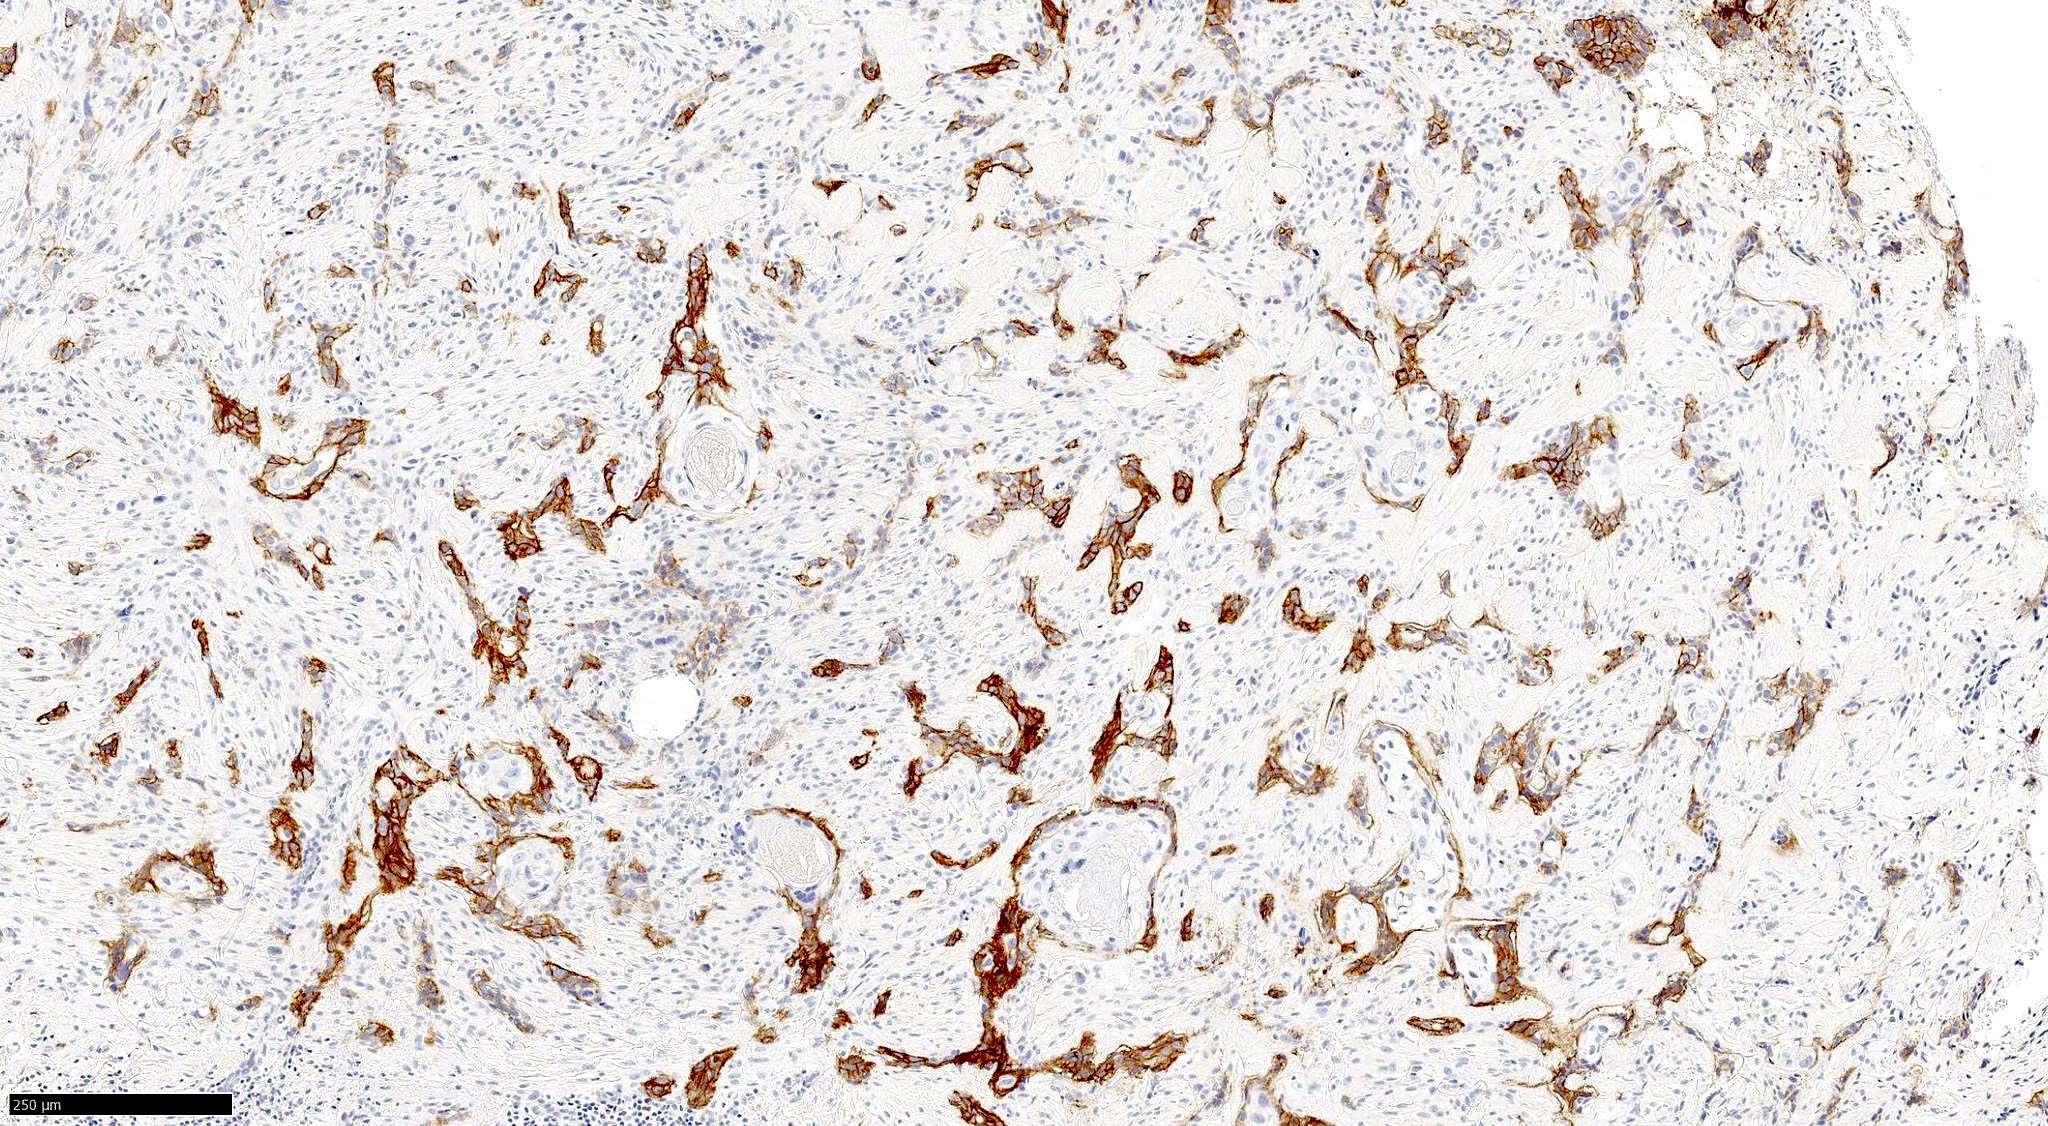

- Pigmented BCC

- Nodular and superficial variants can be pigmented

- Colonization of tumor's complexes with melanocytes

- Stromal melanophages

Microscopic (histologic) images

Contributed by Antonina Kalmykova, M.D., Phillip H. McKee, M.D., Sate Hamza, M.D., Eduardo Calonje, M.D.,

Wayne Grayson, M.B.Ch.B., Ph.D., James Sampson, M.B.B.S., M.Sc. and Assia Bassarova, M.D., Ph.D.

Positive stains

- CK AE1 / AE3 (100%), BerEP4 (80 - 100%), p63 (100%), CAM 5.2 (20 - 95%), androgen receptor (33 - 66%), p53 (74.5 - 83%), 34 beta E12 (high molecular weight CK), BCL2 (diffuse pattern), CD10 (positive in tumor cells, negative in stroma) (Dermatopathology (Basel) 2015;2:15, Arch Pathol Lab Med 2017;141:1490, Rom J Morphol Embryol 2018;59:1115, Am J Pathol 1992;141:25)